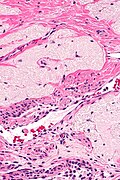

Ablated_endometrium. H&E stain. | |

| LM | endometrium completely or partially replaced by hyaline material and fibrosis |

- Endometrium completely or partially replaced by:

- Hyaline material, fibrosis.

UTERUS, UTERINE CERVIX, TOTAL HYSTERECTOMY: - SUPERFICIAL FIBROSIS AND HYALINE CHANGE OF THE UTERINE LINING -- COMPATIBLE WITH PRIOR ABLATION. - UTERUS WITH LEIOMYOMAS. - UTERINE CERVIX WITHIN NORMAL LIMITS.